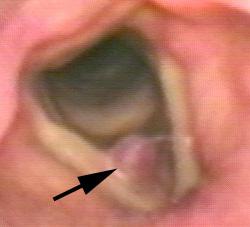

声带息肉(vocal polyp)是发生于声带固有层浅层的良性增生性病变,也是一种特殊类型的慢性喉炎。最主要的临床症状为声嘶。通过喉镜检查可以做出临床诊断。治疗方式主要为手术切除治疗。若经治疗好转后,患者仍暴露于用声过度、用声不当、吸烟等危险因素中,则声带息肉可再次出现。术后要继续避免和治疗可能的致病因素